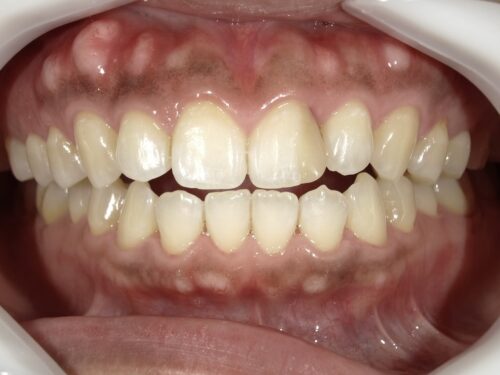

真正面だけでなく、

横から見たり、

噛む面から見たりと、この詰め物の状態をよく確認します。

また、

レントゲンでも詰め物の奥で再びむし歯になっていないか等、

色以外にほかに問題点がないか検査が必要です。

今回はとくに問題ありませんでした。